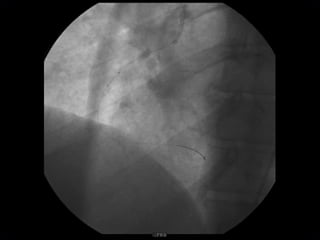

RECANALIZAÇÃO MECÂNICA COM GUIA 0,014mm

PRE-DILATAÇÃO COM CATÉTER BALÃO

CATÉTER DE ASPIRAÇÃO PRONTO – V3